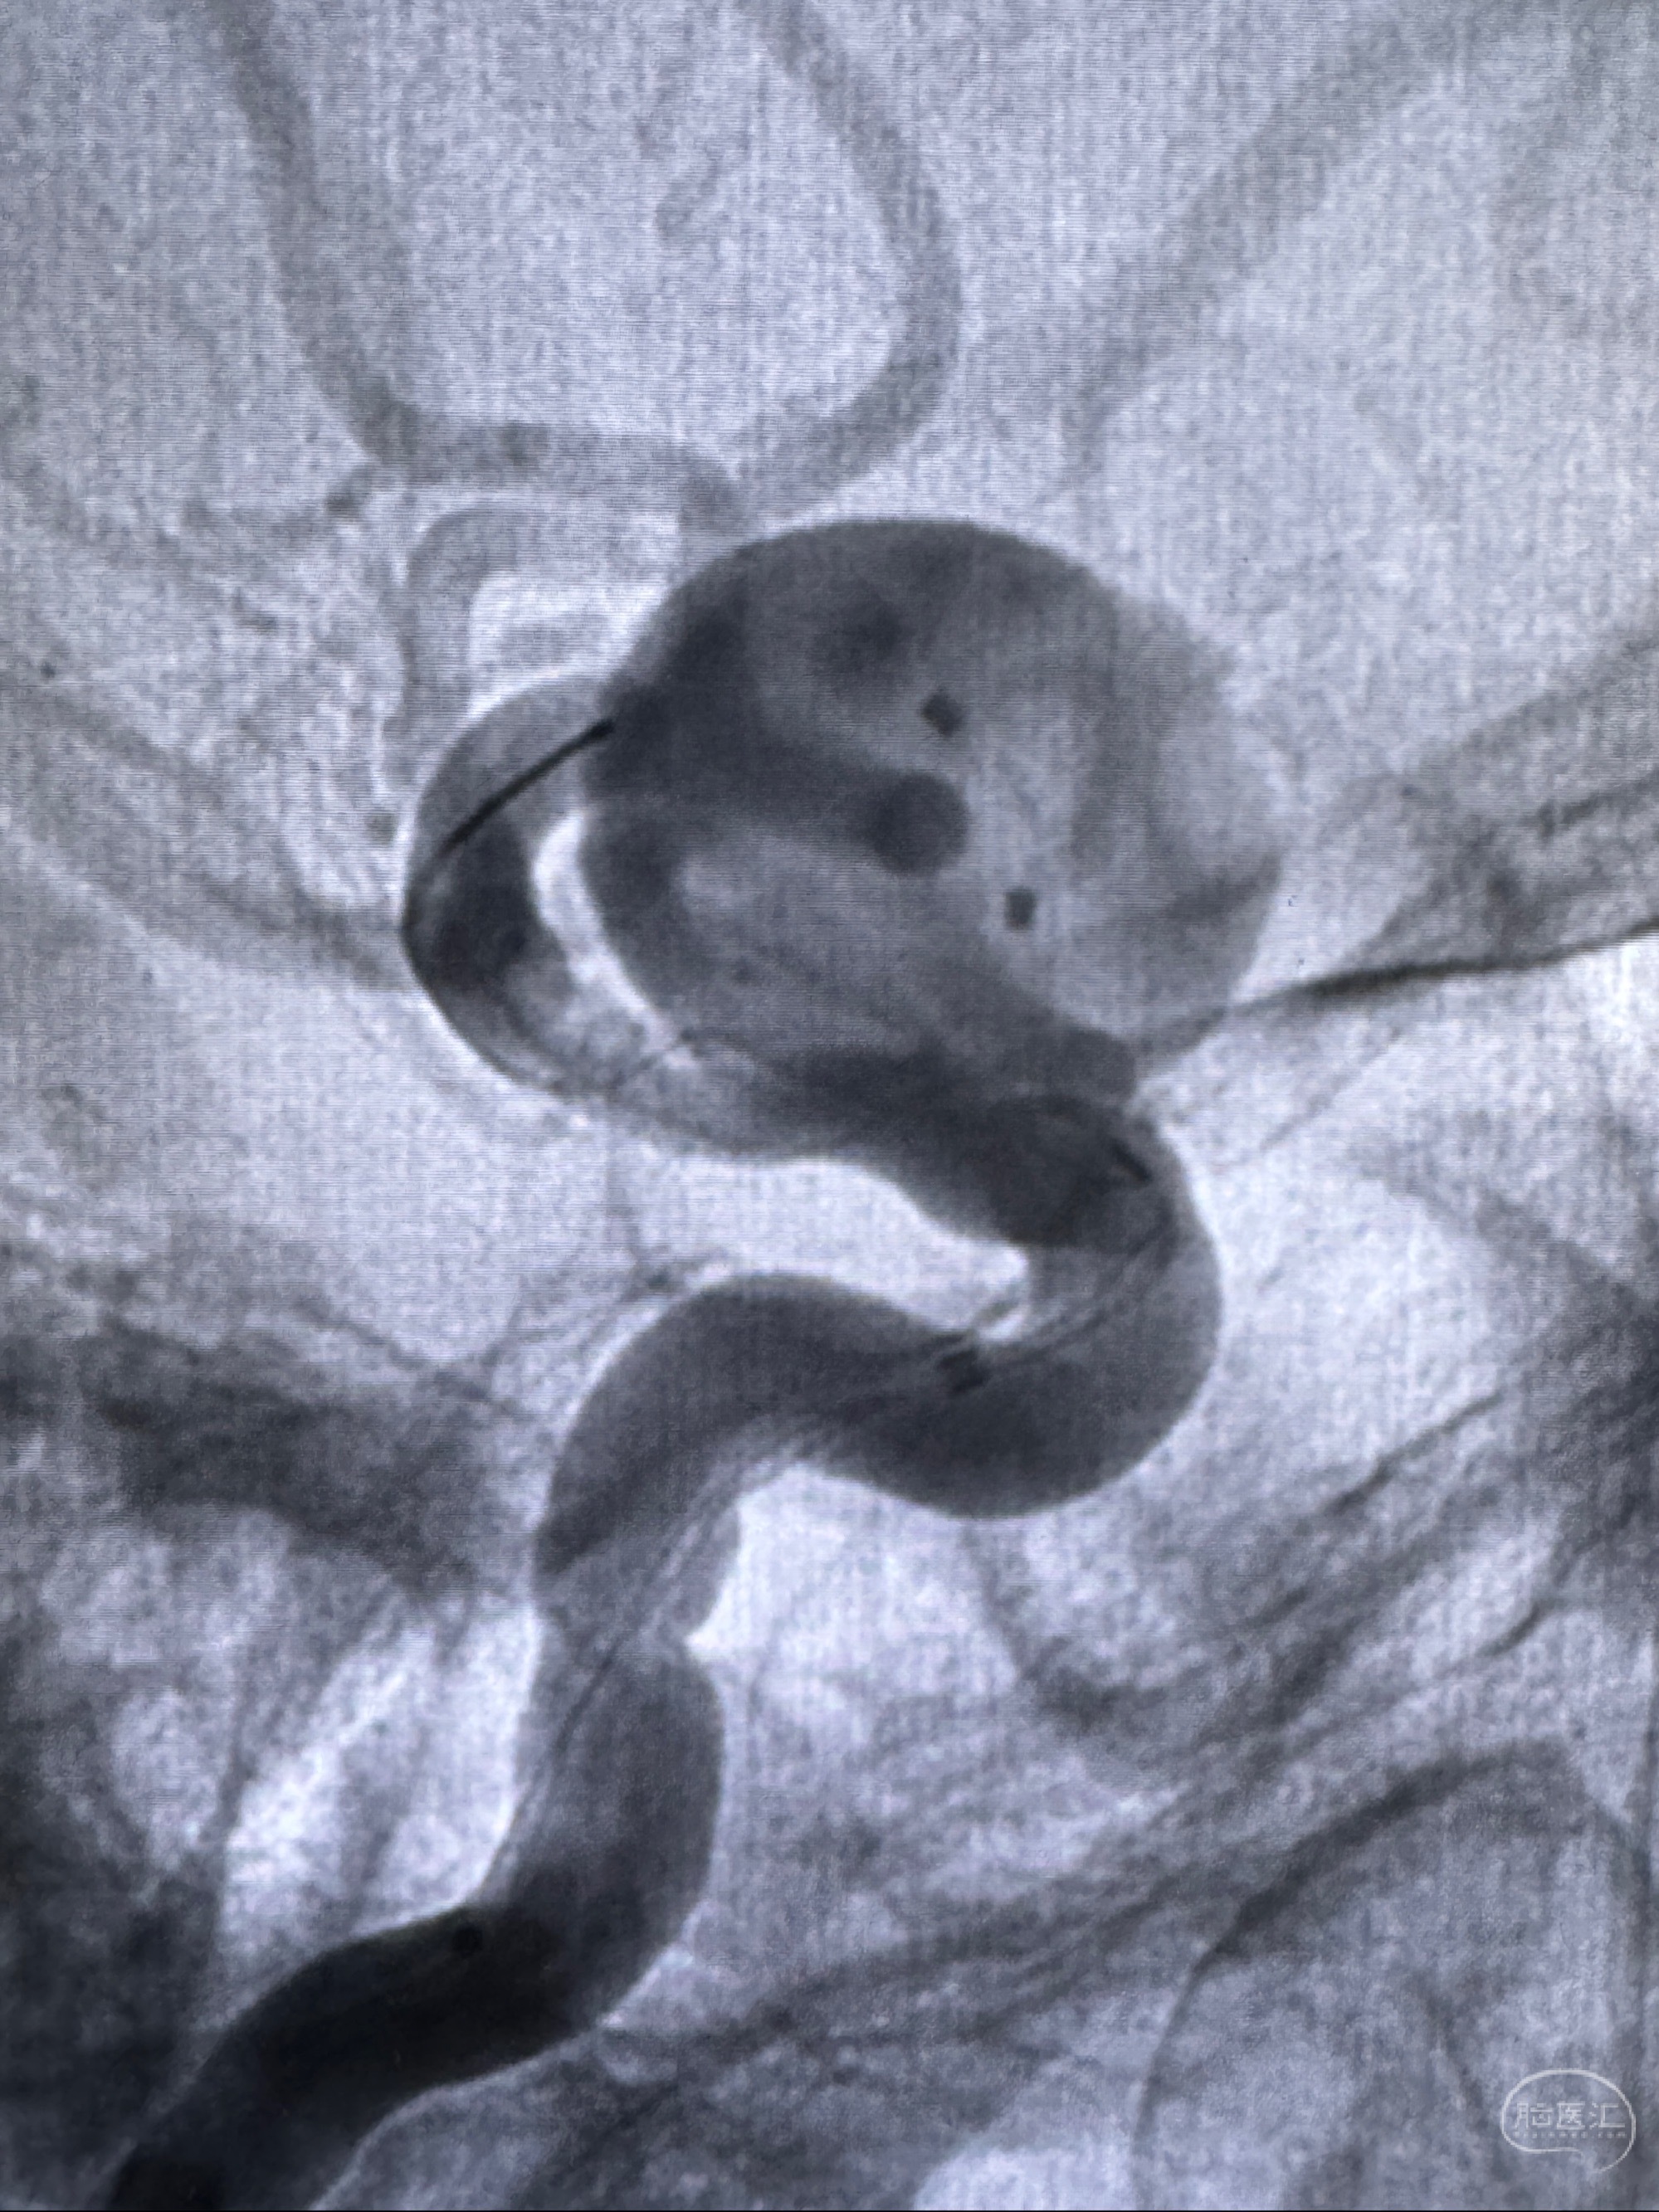

旋转3D展示动脉瘤局部的血管构筑

测量动脉瘤的大小:16*13.8*7.6mm大小,较原先变大,考虑双抗后瘤内血栓溶解可能

观察动脉瘤腔内的血流动力学情况

造影显示支架贴壁情况

再次造影确认支架贴壁情况